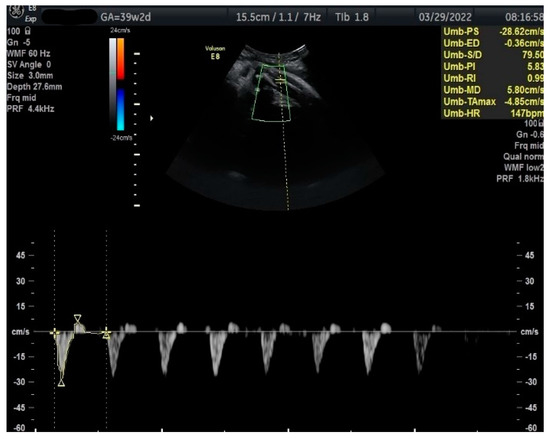

Figure 2.

Doppler measurement at 38 + 0 weeks of normal TA-PI (measured manually).

Measurements of the TA-PI were taken using Doppler on the lower extremity where the tibial and fibular bones were clearly visible. The angle between the transducer and the bones was adjusted to 45° or less. The color Doppler gate was placed over the vessel in the leg between the two bones to locate the anterior TA (Figure 1). We were able to measure the velocity of the TA in all fetuses, signals were recorded over at least 5–6 cycles with an equal shape and amplitude of the blood flow waveforms (Figure 2 and Figure 3).

Doppler measurement at 39 + 2 weeks of TA-PI shows reverse flow >95th percentile (measured manually).